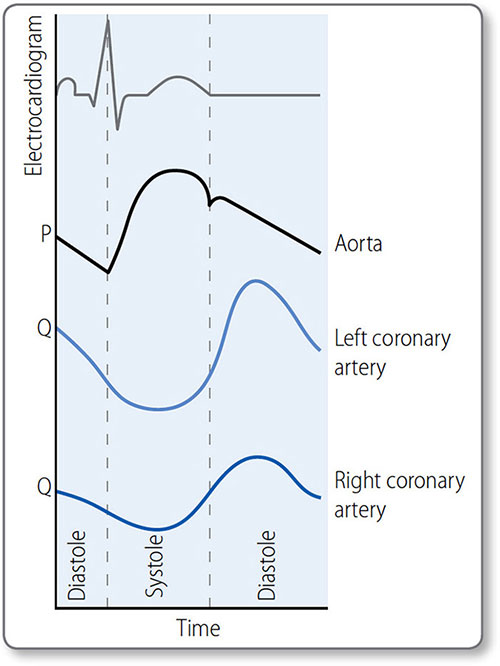

Coronary blood flow

Contrary to other organs, coronary blood flow is impeded during systole and enhanced during diastole, particularly on the more muscular left side. The transmural pressure generated by systole compresses subendocardial arterioles so that myocardium is not perfused. Some systolic perfusion does occur in the outermost (i.e. subepicardial) myocardium, where transmural pressure is lower.

Left coronary artery flow

The highest LCA flow occurs during diastole (Figure 1.32). The lowest is during the isovolumetric phases of systole, when ventricular pressure is high but coronary flow is low.

Right coronary artery flow

Right ventricular myocardial perfusion is more consistent as wall tension is much lower than in the left.

Figure 1.32: Coronary blood blow (schematic representation). Aortic pressure (P) peaks in systole; left coronary artery (LCA) flow (Q) peaks in diastole, due to high systolic resistance caused by compression of vessels in the ventricular wall. This effect is less in the right coronary artery (RCA) as right ventricular pressures are lower.